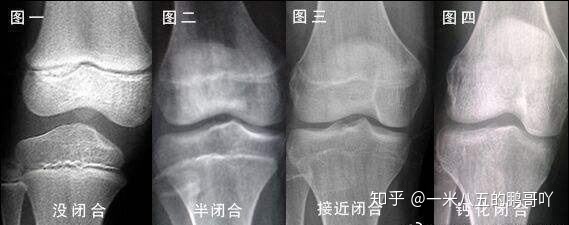

骨骺线闭合图

骨骺的闭合情况